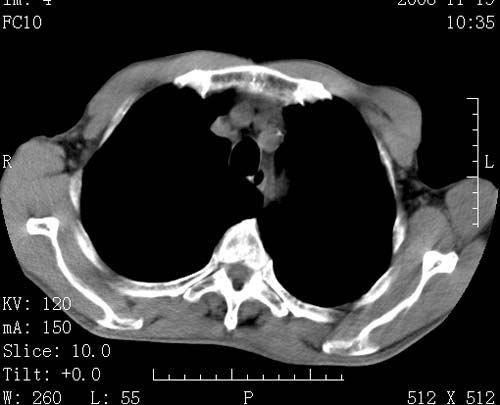

标题: CT16691:m 67 胃镜确诊食管下段及贲门癌 [打印本页]

标题: CT16691:m 67 胃镜确诊食管下段及贲门癌

术前查体,双肺部结节是转移?结核?请点评

1)符合食管癌表现。2)两肺及纵隔淋巴结多发性转移瘤。3)左肺上叶舌段及两肺下叶炎症感染。

1)符合食管癌表现。2)两肺及纵隔淋巴结多发性转移瘤。3)左肺上叶舌段支气管扩张伴感染.

食管癌伴双肺转移,评述:肺部毛细血管网丰富,全身血液均快速流经肺部,癌细胞容易过滤定植,形成转移瘤,影象特点为以毛细血管末梢为中心的结节灶,边缘光滑锐利,少见有中心空洞着,不同来源的转移瘤可有各自特点,如甲状腺癌为双肺弥漫性微结节,本例有原发灶,双肺影象灶典型,左肺舌段条带状网格样伴胸膜天幕征,可视为癌性淋巴管炎。

左肺舌段有斑点钙化灶,能否说明是结核而不是转移?如果是转移将放弃手术改成化疗,如果是结核将考虑择期手术